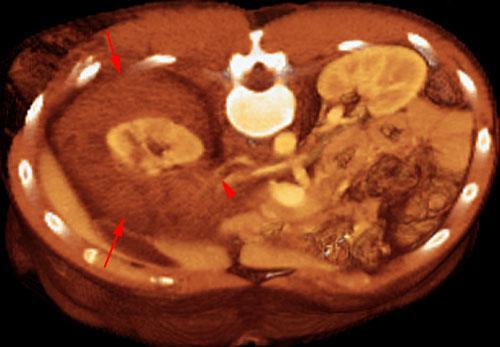

Rotura pielocalicial